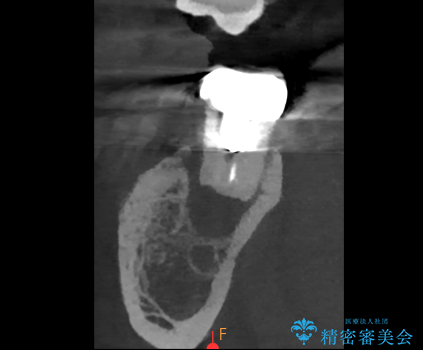

- 過去にヘミセクションが行われていたと思われる左下7番は、大きな歯根嚢胞および根尖病変が認められ、さらに骨縁下カリエスを伴っており、歯肉には瘻孔が形成されている状態でした。

保存は困難と判断し、左下7番は抜歯即時インプラントによる治療を行いました。

抜歯と同時にインプラントを埋入するため、歯茎を切開する必要がなく、術後の痛みが出にくい治療方法です。